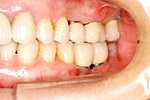

症例 11

① 左右の奥歯がありません。普通では左右つながった取り外しの入れ歯しか入りません。

② インプラントで固定式の義歯ができました。自分の歯に近い感じで食事ができます。

60才代 女性

総額:182万円(税別)

治療期間:6ヵ月

リスク副作用:メインテナンス不良ですと歯周炎、インプラント周囲炎になります。セラミックが欠けることがあります。